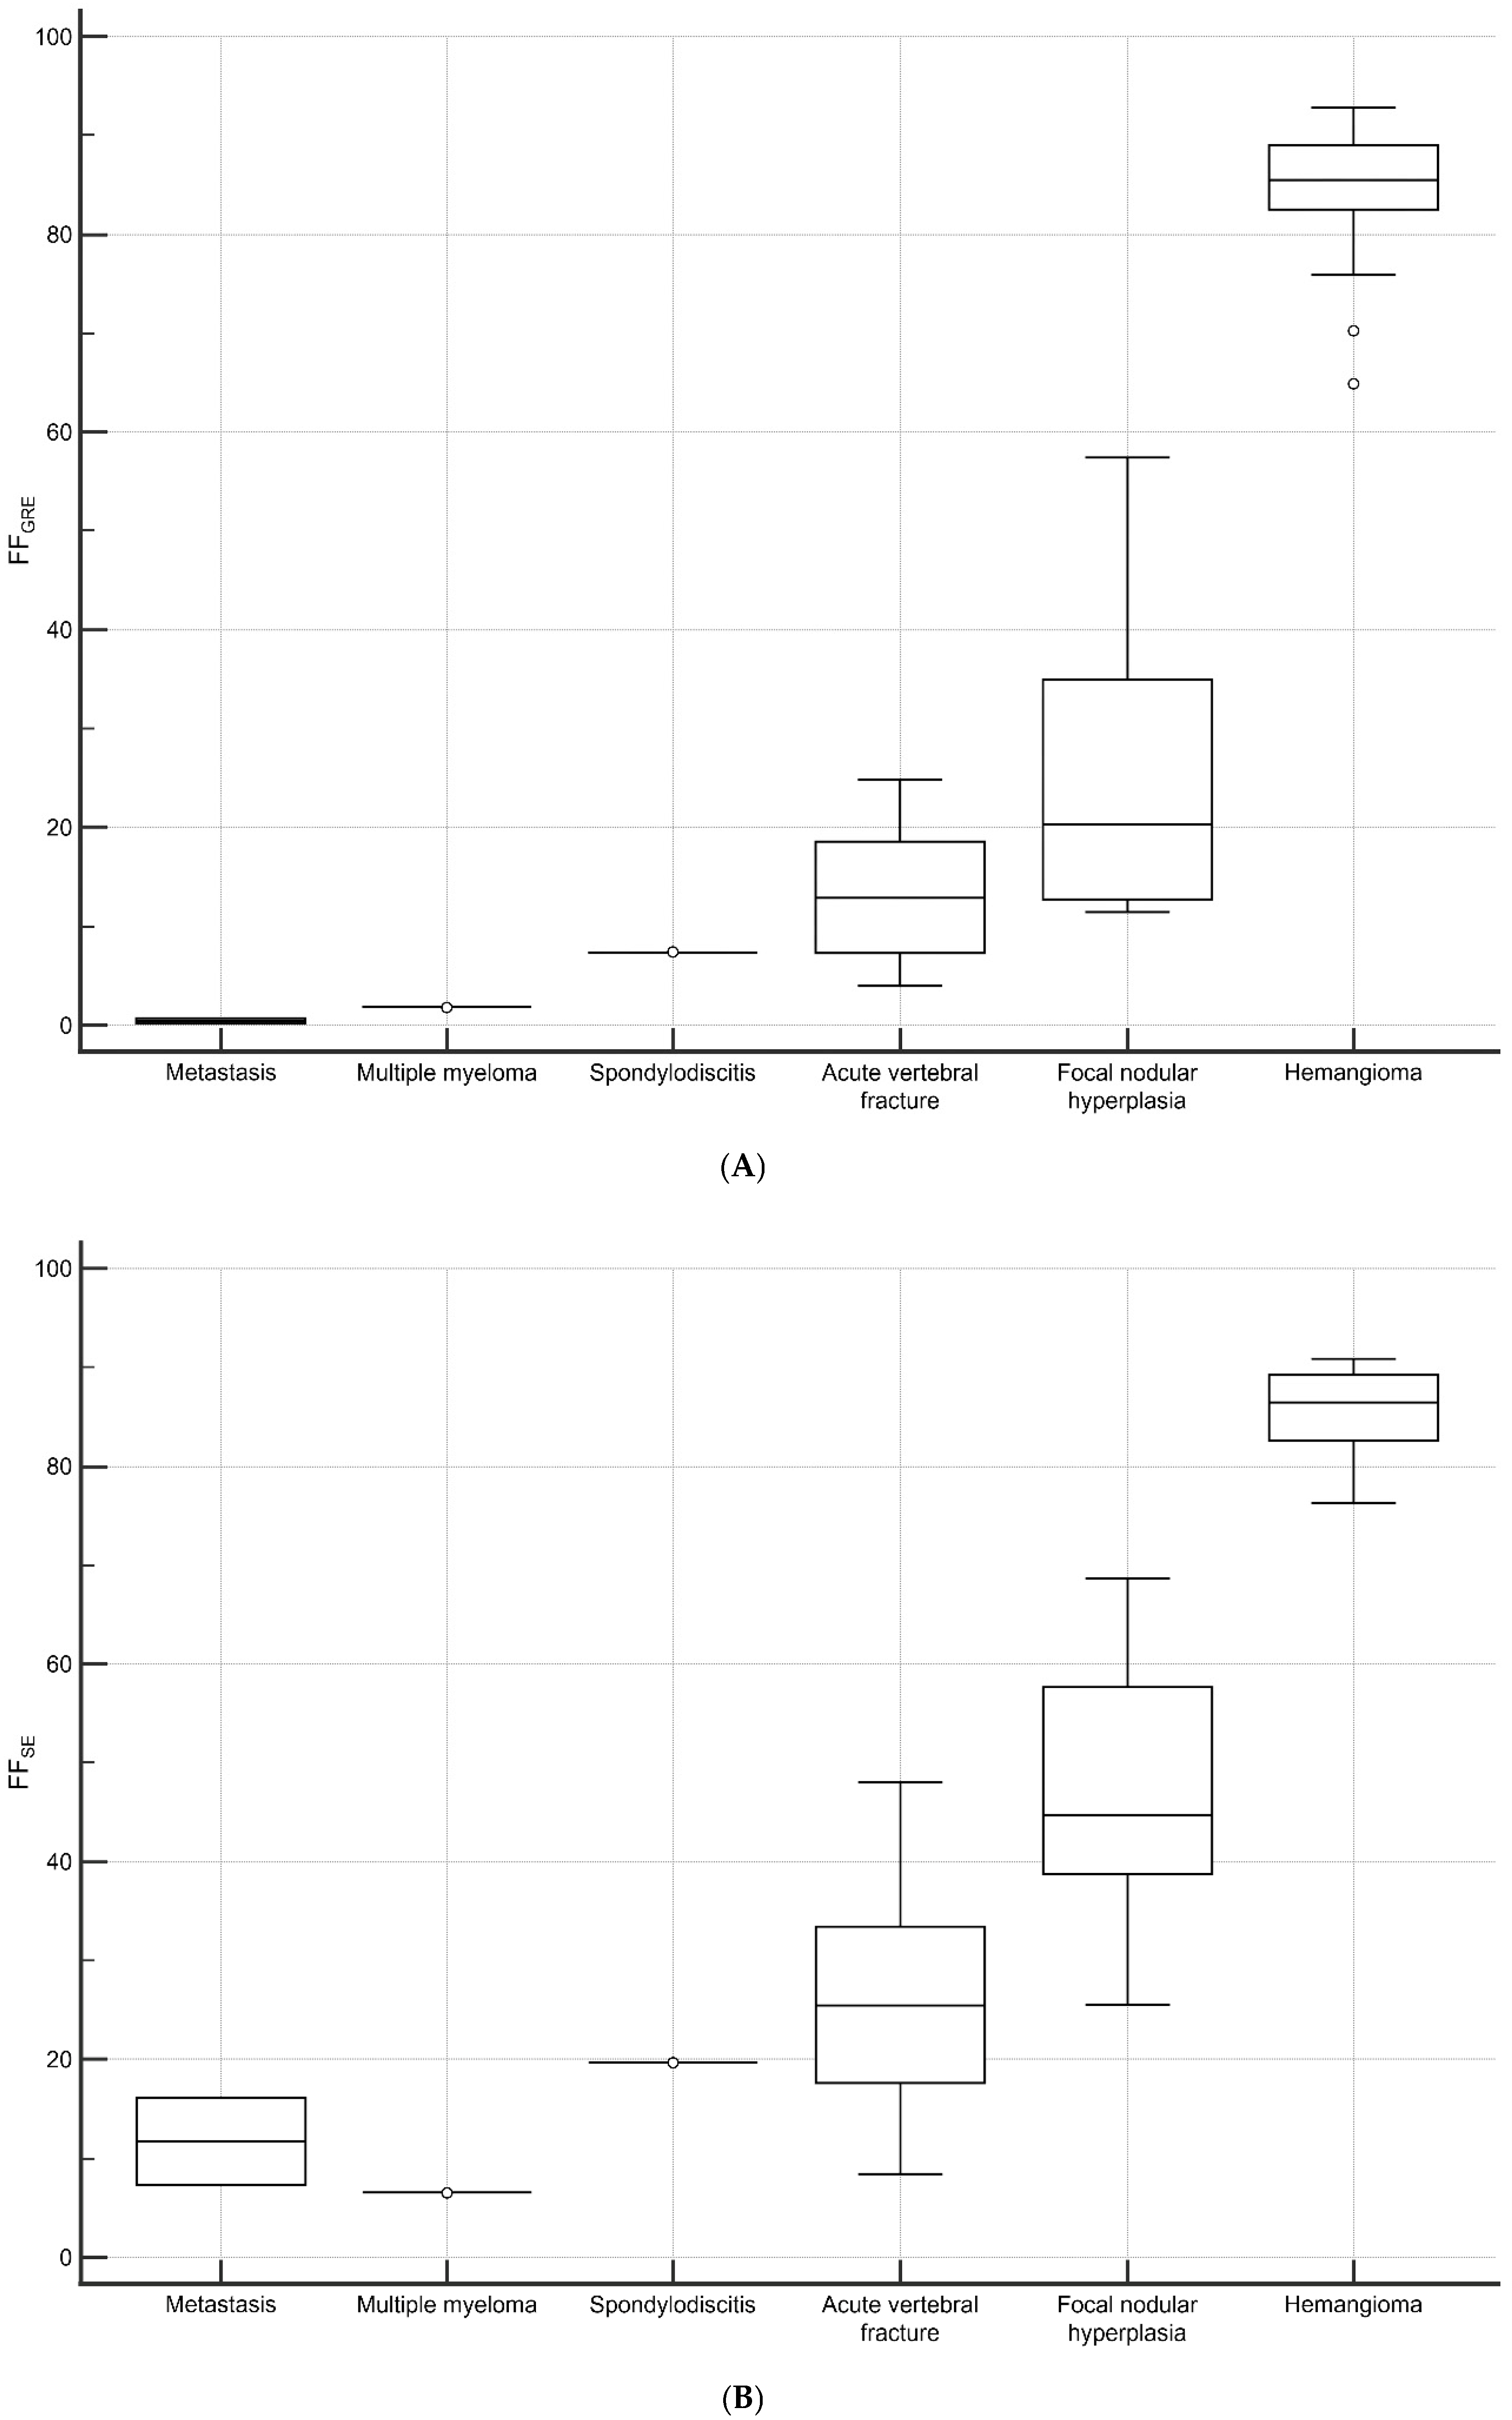

3.4. Vertebral Lesions Analyses